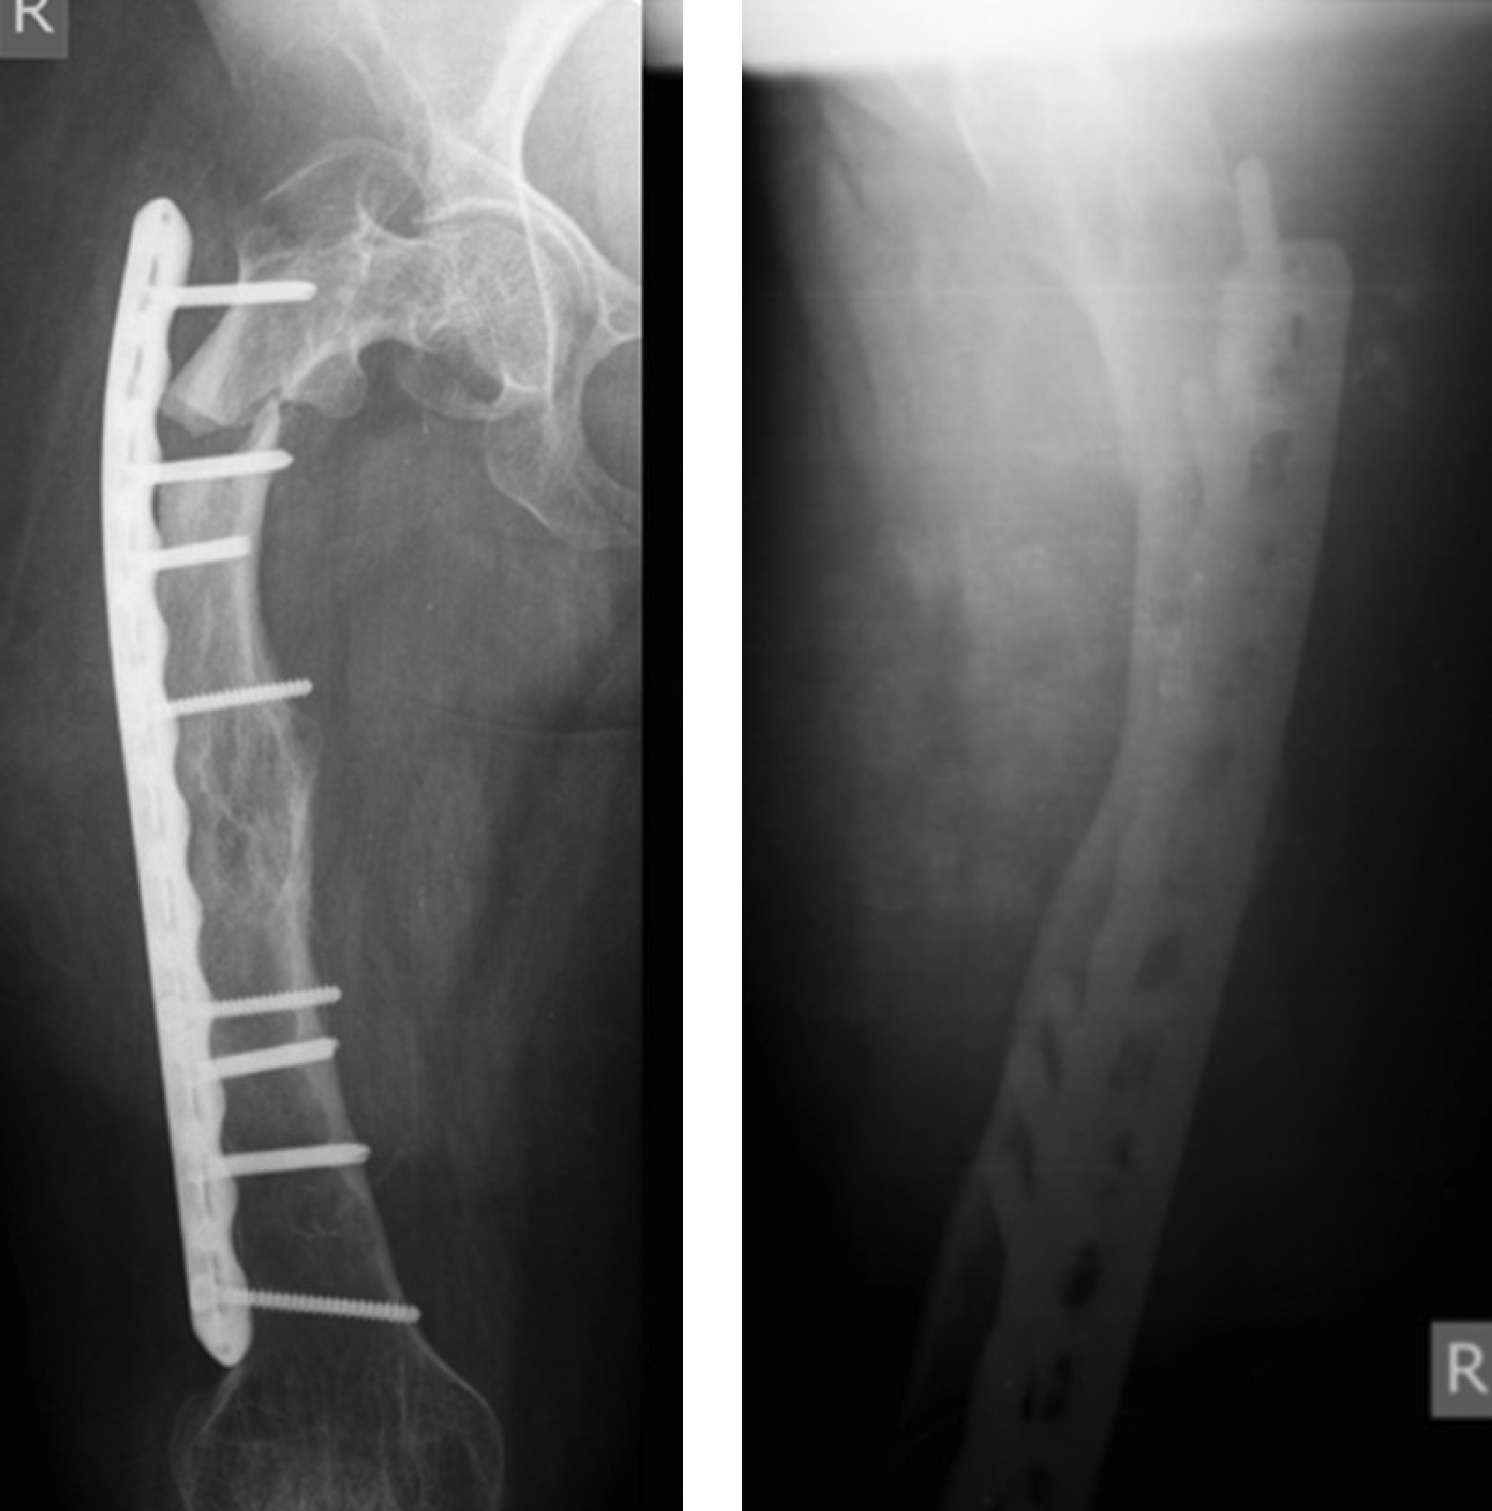

Несмотря на достигнутую консолидацию перелома проксимального отдела правой бедренной кости, рентгенологически прослеживается его зона, что характерно для НО (рис. 7). Ось оперированной бедренной кости близка к оси здоровой кости (рис. 8).

Рисунок 7. Рентгенограммы правой бедренной кости пациентки 5 лет и 4 месяца после оперативного вмешательства.

Рисунок 8. Осевые рентгенограммы нижних конечностей через 5 лет и 4 месяца после оперативного вмешательства на правом бедре.